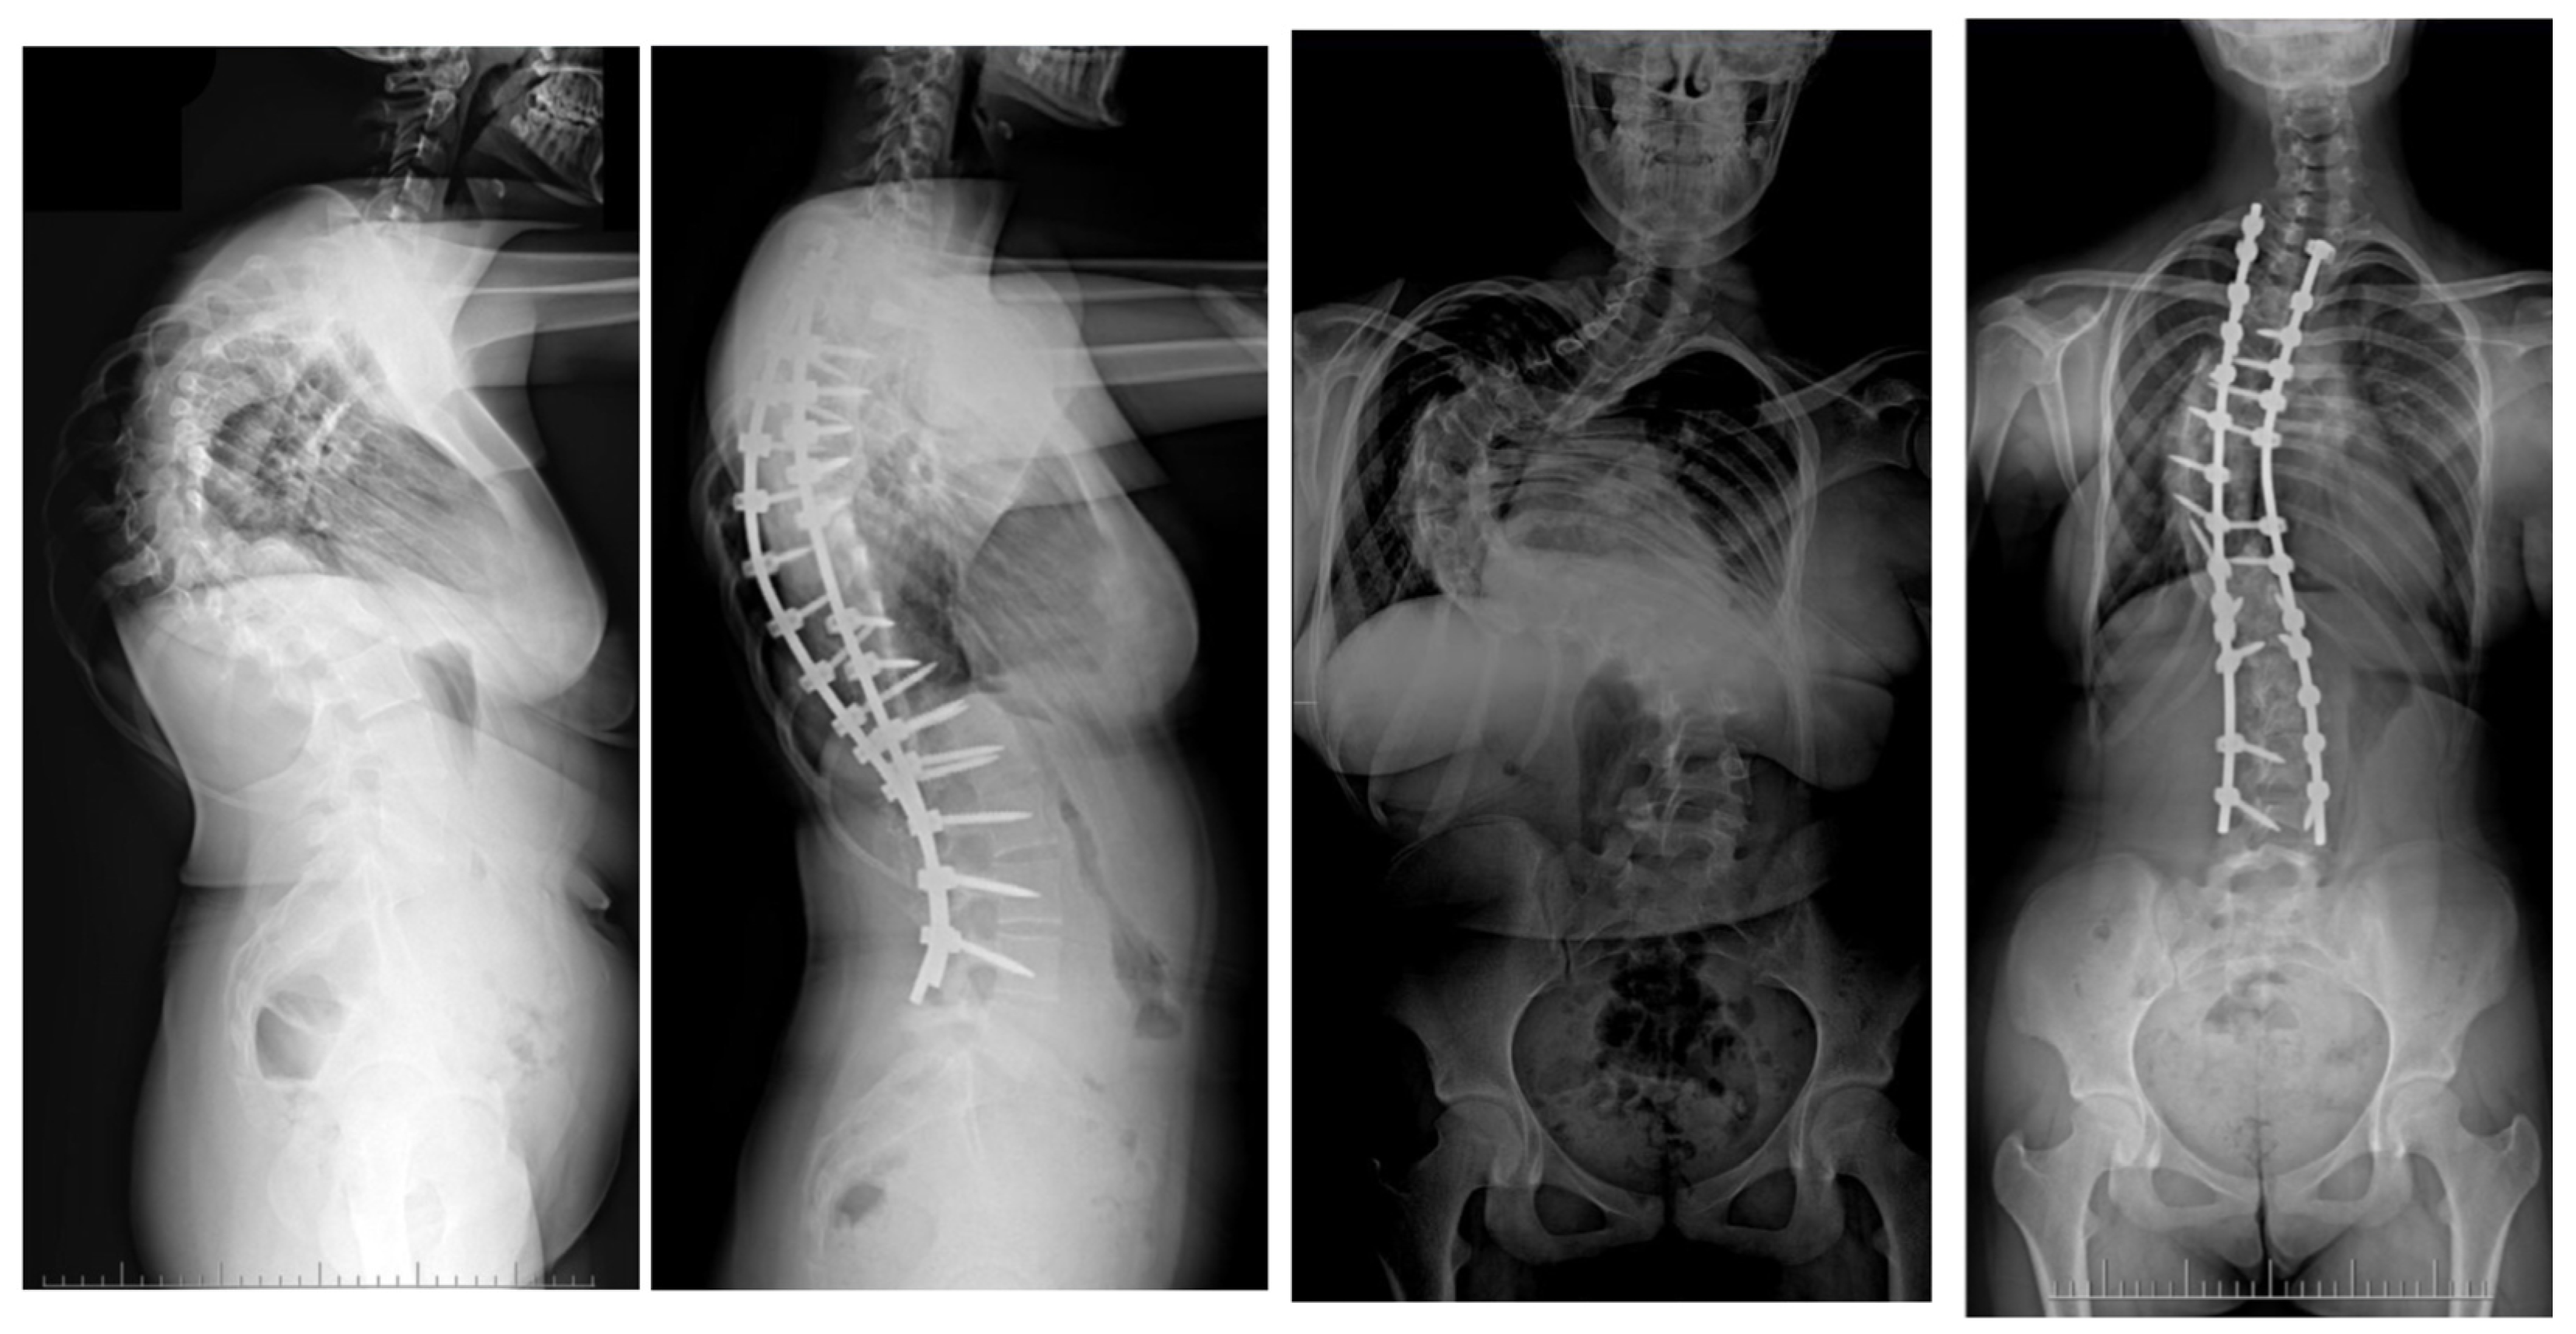

Surgical Treatment Strategies for Severe and Neglected Spinal Deformities in Children and Adolescents without the Use of Radical Three-Column Osteotomies

10. Rib Resection/Thoracoplasty